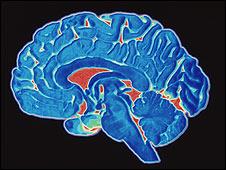

Los daños de la marihuana fueron documentados con imágenes del cerebro realizadas con la última tecnología, y fueron más notorios en personas que comenzaban a consumirla a muy temprana edad.

Los disturbios que se comprueban con las imágenes indican que se producen a nivel de la conectividad, especialmente en las fibras del hipocampo y las fibras de las comisuras, que corresponden a la zona de la memoria y aprendizaje.

La investigación consistió en comparar las imágenes de resonancia magnética y otros métodos, en 59 consumidores de Cannabis por muchos años, y en 33 no consumidores se detectaron las áreas del cerebro deterioradas.